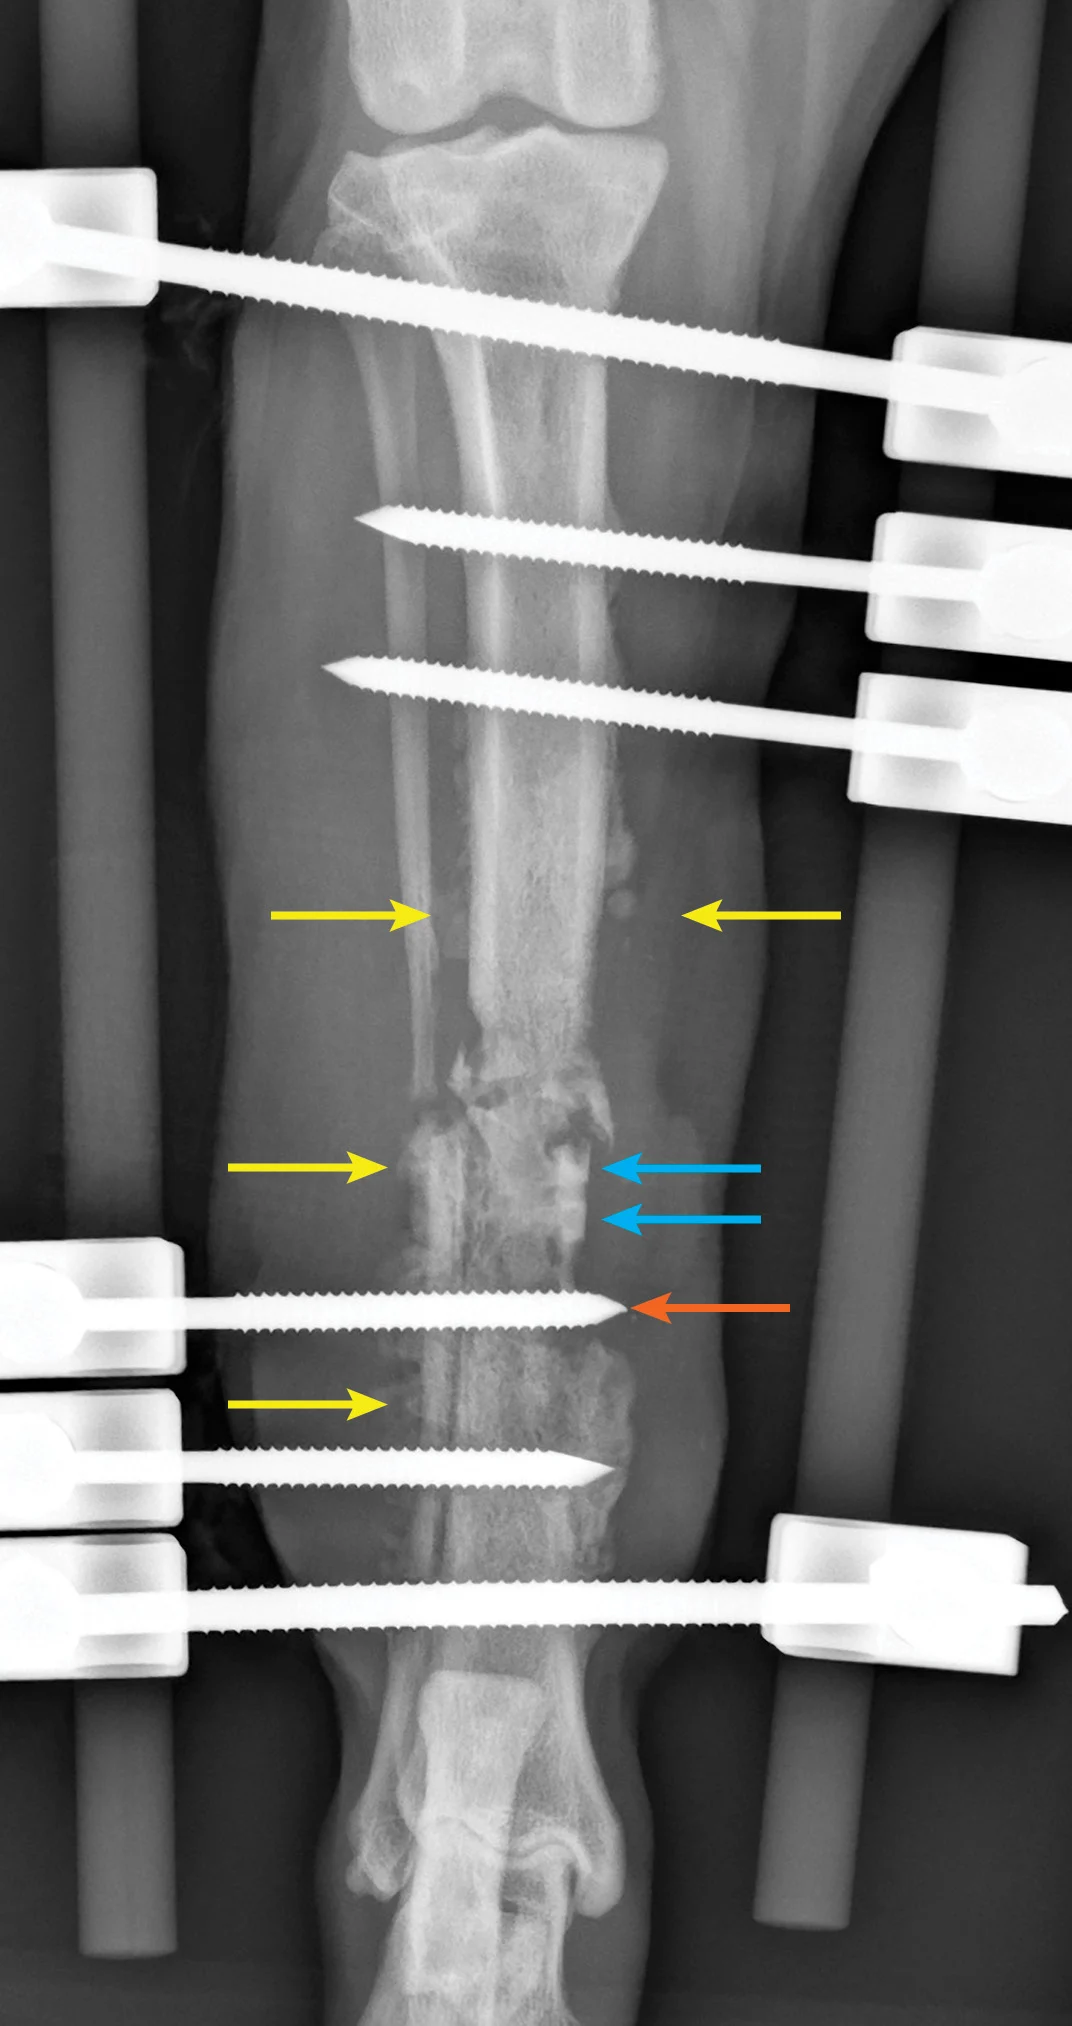

Clindamycin has great bone penetration; however, as a lincosamide antibiotic, it is bacteriostatic and, therefore, should not be given in combination with a bactericidal drug. Clindamycin affects bacteria via inhibition of protein synthesis of the bacterial ribosome and has excellent activity against most pathologic anaerobic bacteria; most aerobic gram-positive cocci (eg, staphylococci, streptococci) are also susceptible. This drug is often effective against Corynebacterium spp, Nocardia asteroides, and Mycoplasma spp. It is FDA-approved for treating osteomyelitis (Figure) in dogs (11-33 mg/kg PO q12h) and cats (11-33 mg/kg PO q24h).13

Craniocaudal radiograph of a postoperative (8 weeks) open tibial fracture with tibial/fibular osteomyelitis. Note the large degree of soft tissue swelling, spiculated periosteal response (yellow arrows), sequestrum (blue arrows), and loose transfixation of the pin on the external skeletal fixator (orange arrow). Successful treatment of this patient’s infection required a multimodal approach including removal of the sequestrum, debridement of necrotic material and biofilm, removal and replacement of the loose transfixation pin, and antibiotics based on culture and susceptibility testing of deep wound tissue.